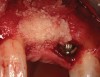

A 53-year-old woman presented with a failing implant in the No. 7 site (Figure 12 and Figure 13). Her desire was to eliminate infection and preserve esthetics. A team effort between the periodontist and restorative dentist to advocate for additional restorative dentistry as well as manage the patient’s expectation of time required was essential. In addition, the patient needed to have realistic expectations of a compromised outcome. Both the restorative dentist and the periodontist informed the patient about the difficulty of achieving this with acceptable esthetic results. Mutual emotional and technical support was required to successfully complete this case, from initial grafting of the defect to placement of anterior restorations (Figure 14 through Figure 23).